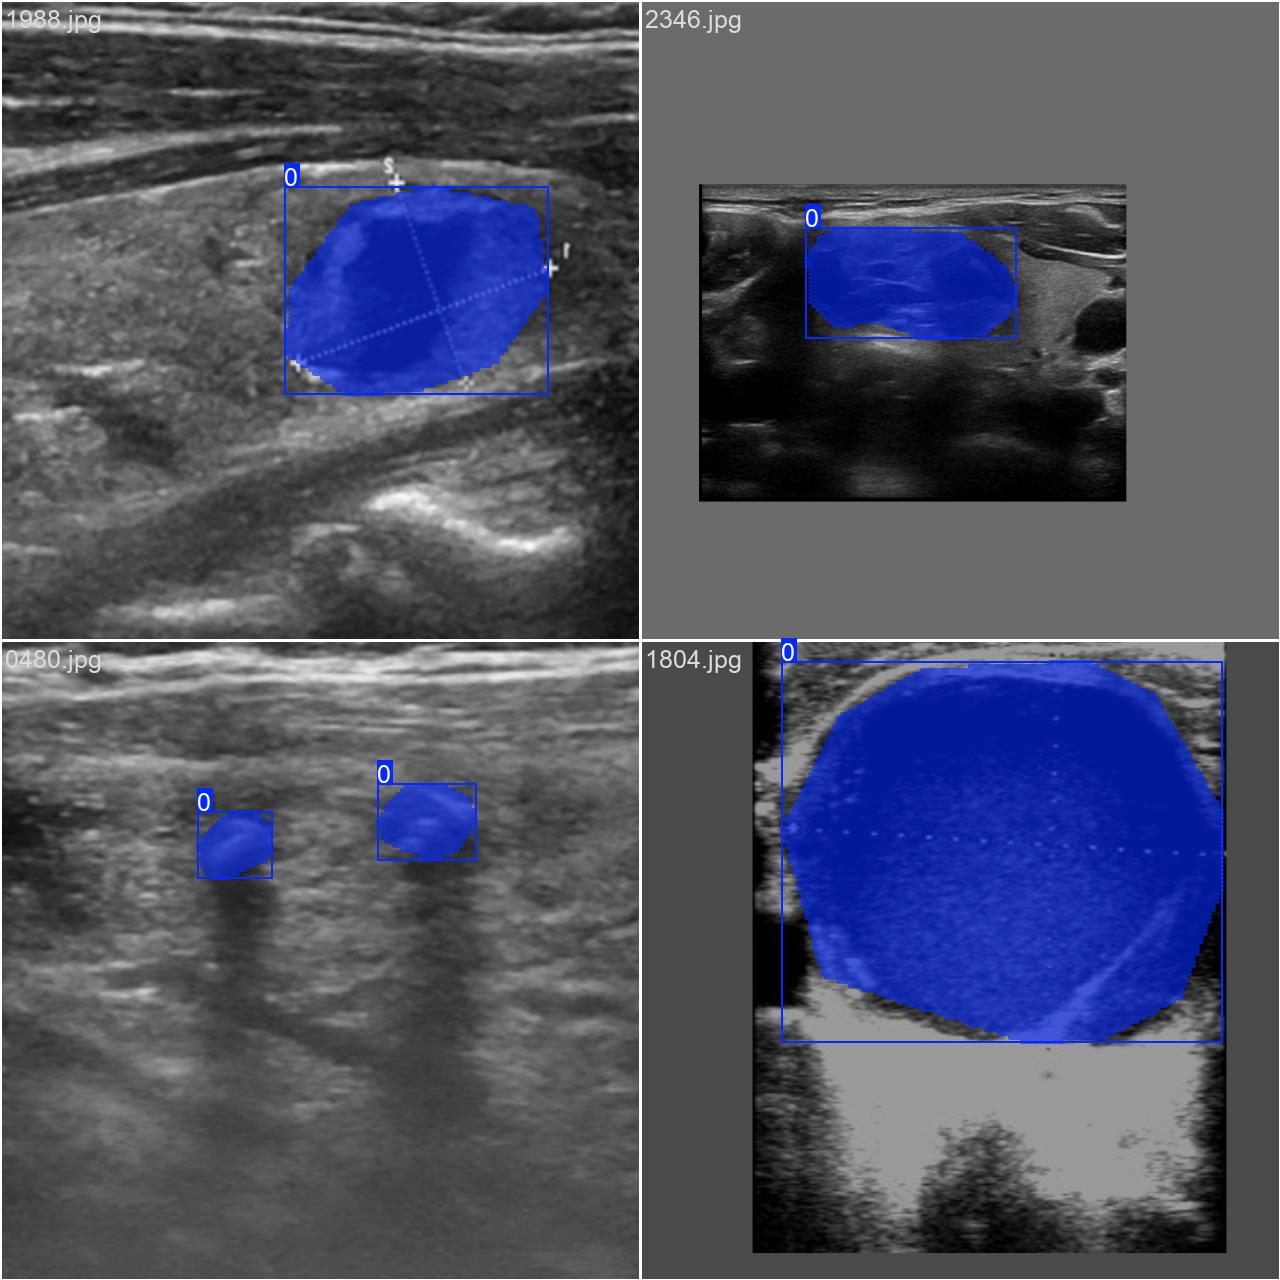

通过网络上搜集关于超声图像的甲状腺结节图片,并使用Labelme标注工具对每张图片中的分割结果及类别进行标注。一共包含3493张图片,其中训练集包含2879张图片,验证集包含614张图片,部分图像及标注如下图所示。